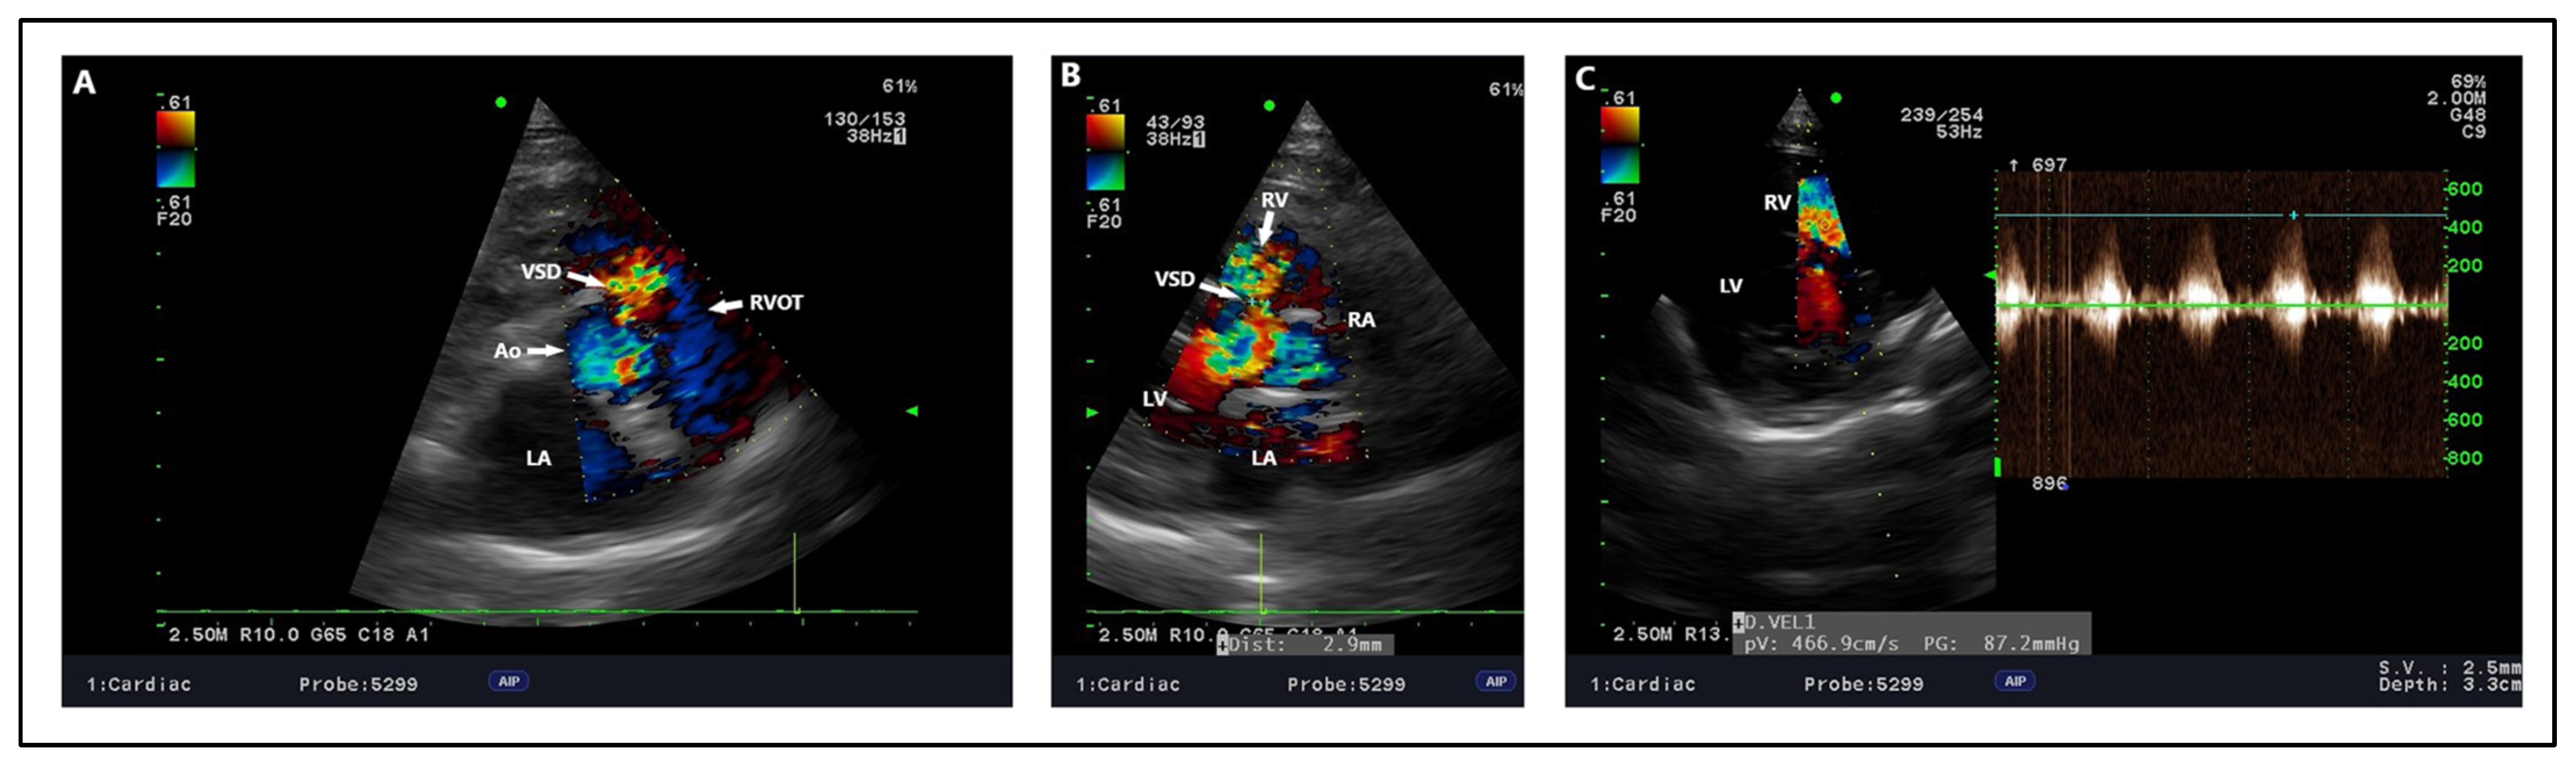

Figure 7.

Proposed echocardiographic projections with explanations of the geography of the ventricular septal defect. (A) Right parasternal short-axis view at the level of the aortic valve—the optimal projection for obtaining a view of the outlet and perimembranous ventricular septal defect. (B) Right parasternal short-axis view at the level of the mitral valve—optimal for imaging trabecular muscular and inlet ventricular septal defect. (C) Right parasternal short-axis view at the level of the papillary muscles—a non-angled oblique projection, excluding the medial papillary muscle to optimize imaging on trabecular muscular and inlet ventricular septal defects. (D) Right parasternal four-chamber long-axis view—optimal for trabecular muscular ventricular septal defect. (E) Right parasternal modified five-chamber long axis view—optimal for predominantly central perimembranous ventricular septal defect. (F) Left apical four-chamber view—optimal for inlet and trabecular muscular ventricular septal defect. (G) Left apical three-chamber view—optimal for obtaining trabecular muscular and perimembranous ventricular septal defect. With a lot of experience of the examiner and maneuvering of the ultrasound transducer, it is also possible to capture the outlet ventricular septal defect. Green color—perimembranous ventricular septal defect. Blue color—inlet type ventricular septal defect. Red color—trabecular muscular ventricular septal defect. Purple color—outlet type ventricular septal defect.